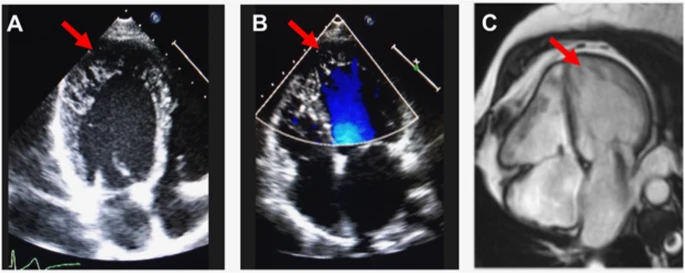

Bác sĩ sử dụng một số xét nghiệm để chẩn đoán bệnh cơ tim xốp, bao gồm:

- Siêu âm tim để đánh giá cách tim bơm máu.

- Các xét nghiệm hình ảnh, bao gồm chụp CT tim và MRI, để xem cấu trúc tim của bạn.